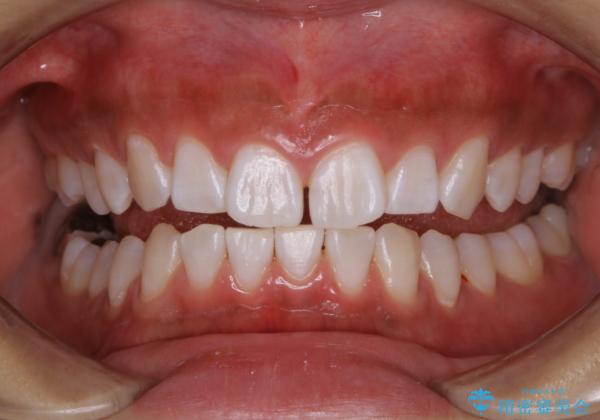

この患者様は、歯科矯正に1、2年かかり矯正中はホワイトニングをすることが出来ないため、歯を白くしてから矯正治療にすすみたいとのことでオフィスホワイトニングを行いました。1回の施術で2.3トーン白くなり、とても白くなりました。ホワイトニングは何度も重ねて白くしていくのですが、1度で満足のいく色見になったため一旦様子を見ることにしました。

1ヶ月後来院して頂きチェックしたところ、やはり後戻りがあったため、再度オフィスホワイトニングを行うことになりました。

1回のオフィスホワイトニングですとこのくらいの後戻りがあるため、ホワイトニングを考えている方は是非参考にしてください。